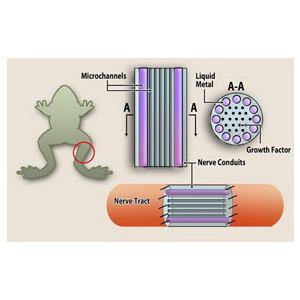

жґ≤жАБйЗСе±ЮжШѓдЄАе§Із±їе§ЪйЗСе±ЮеРИйЗСжЭРжЦЩпЉМеЬ®еЄЄжЄ©дЄЛеСИжґ≤жАБпЉМеПѓдї•еЃЮзО∞еЫЇзЫЄеТМжґ≤зЫжАєЛйЧізЪДзБЙ|іїиљђжНҐеQМеЕЈжЬЙеѓЉзФЙ|АІеЉЇгАБеѓЉзГ≠зОЗйЂШгАБзЖФзВєеПѓжОІз≠ЙзЙєзВєеQМжЧ†йЬАйЂШжЄ©еЖґзВЉеQМзОѓдњЭжЧ†жѓТпЉМиХіеРЂзЭАиѓЄе§ЪЉЬЮе•ЗзЪДзЙ©зРЖгАБеМЦе≠¶дєГиЗ≥зФЯзЙ©е≠¶зЙ“ОАІпЉМеПѓеєњж≥ЫињРзФ®дЇОиИ™з©Їиș姩гАБеЖЫеЈ•еЫљйШМ”АБзФЯзЙ©еМїзЦЧгАБжХЩиВ≤жЦЗеМЦз≠ЙйҐЖеЯЯгА?/span>

дЇСеНЧдЄ≠еЃ£жґ≤жАБйЗСе±ЮзІСжКАжЬЙйЩРеЕђеПЄжИРзЂЛдЇ?013тq?0жЬИпЉМдљНдЇОдЇСеНЧзЬБеЃ£е®БеЄВиЩ“О°•еЈ•дЄЪеЫ≠еМЇеQМжШѓдЄАеЃґдЄУж≥®дЇОжґ≤жАБйЗСе±ЮжЭРжЦЩгАБеКЯиГљеЩ®дїґгАБи£Ее§ЗеИґйА†зЪДз†ФеПСгАБзФЯдЇІдЄОйФАеФЃзЪДйЂШзІСжКАдЉБдЄЪгАВзЫЃеЙНпЉМеЈ≤еЊПжИРжґ≤жАБйЗСе±ЮеИґе§ЗеПКЊp’dИЧдЇІеУБзФЯдсФЊU—ЭАБдЄ≠еЫљжґ≤жАБйЗСе±ЮзІСжКАй¶Ждї•еПКдЎУжґ≤жАБйЗСе±ЮдсФдЄЪеПСе±ХжЬНеК°зЪД“зЬБзсФеЕЂдЄ≠ењГдЄАеІФеСШдЉ?rdquo;з†ФеПСгАБж£АЛєЛег^еП∞гАВеЕђеПЄжЛ•жЬЙдЄУеИ?00дљЩй°єеQМе§ЪЩе“ОКАжЬѓеТМдЇІеУБе°Ђи°•еЫљеЖЕе§Цз©ЇзЩљгАВеЕђеПЄзФЯдЇІзЪДеѓЉзГ≠зЙЗгАБеѓЉзГ≠иЖПљ{ЙдсФеУБеЈ≤襀зГ¶ЮЃє{АБиБФжГ≥з≠ЙеЫљйЩЕеЫљеЖЕдЉБдЄЪдљњзФ®гА?/span>

дЄУж≥®дЇОжґ≤жАБйЗСе±ЮжЭРжЦЩгАБеКЯиГљеЩ®дїґгАБи£Ее§ЗеИґйА†зЪДз†ФеПСгАБзФЯдЇІдЄОйФАеФ?/span>

жґ≤жАБйЗСе±ЮеЕЈжЬЙдЉШеЉВзЪДзЙ©зРЖеМЦе≠¶зЙ“ОАІеТМзФЯзЙ©зЫЄеЃєжАІпЉМШqЩдњЭиѓБдЇЖеЕґеПѓдї•еЬ®зФЯзЙ©еМ’d≠¶йҐЖеЯЯеЊЧеИ∞еЇФзФ®гА?